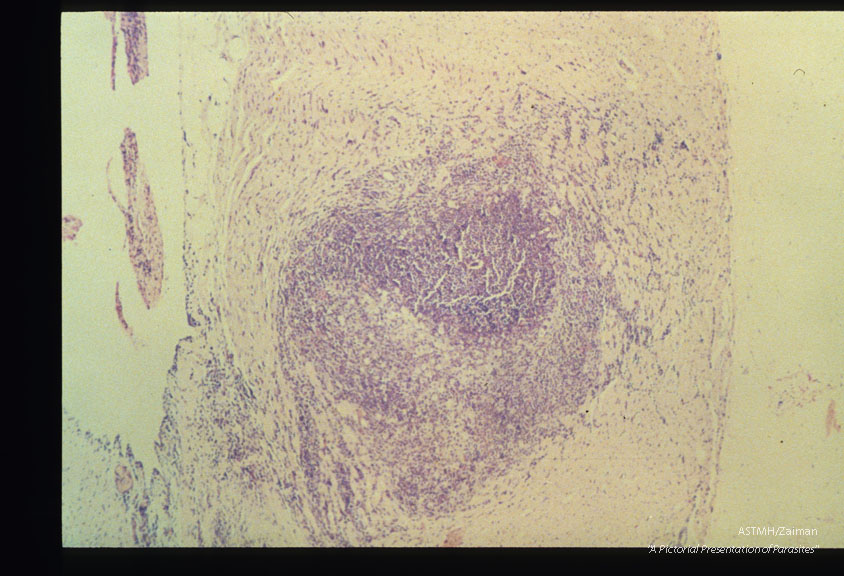

Large eosinophile-rich granuloma occupying almost the entire width of the right ventricular free wall. Naturally infected cat. HE, x 40.

Toxocara canis

Description: Large eosinophile-rich granuloma occupying almost the entire width of the right ventricular free wall. Naturally infected cat. HE, x 40.